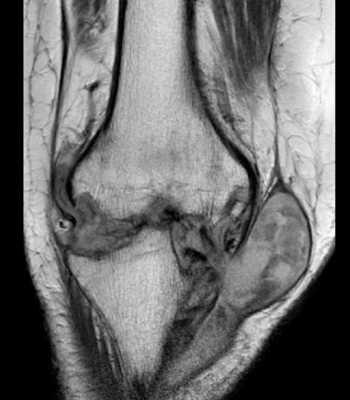

МРТ коленного сустава. Т1-взвешенная корональная МРТ. Септический артрит с абсцессом.